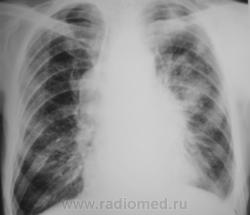

Пациент был взят на контроль в 2009 году, было произведено дообследование в виде томографии в стандартных срезах, был заподозрен очаговый туберкуулёз, который был подтвержден " в области" и пациент был взят на учет. Было назначено специфическое лечение.

Через некоторое время было произведено плановое контрольное обследование.